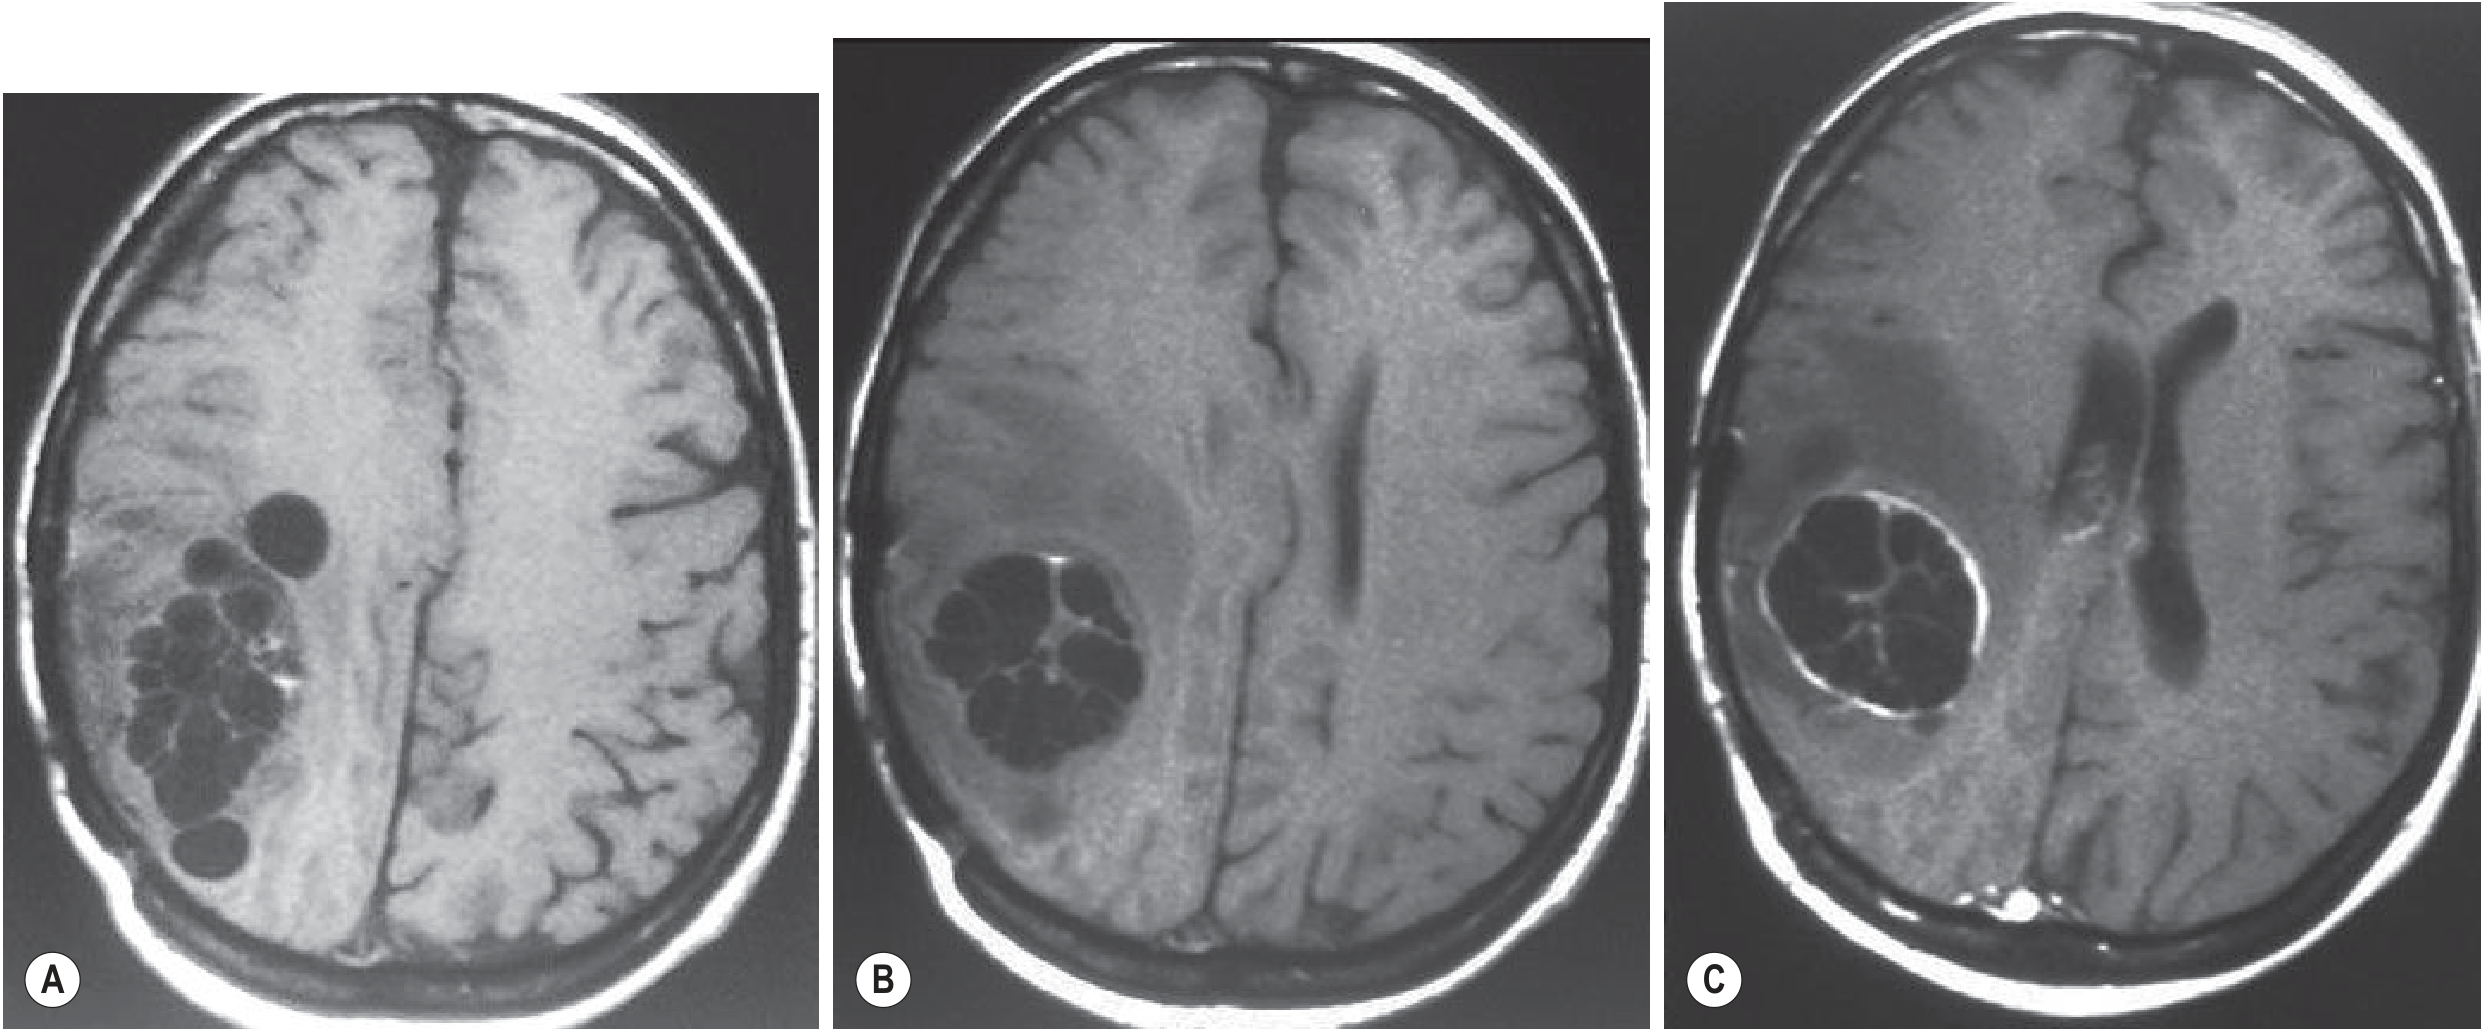

CT: superior for extrahepatic lesions, smaller cysts, precise localization, and surgical planning. MRI: preferred for postsurgical residual assessment, cardiac/intracranial disease, and when ultrasound cannot be performed. Brain MRI (CE): well-defined unilocular cysts with CSF-like fluid; thin rim enhancement and perifocal edema indicate active cyst.

Brain MRI — multiple hydatid cysts with daughter cysts and perifocal edema

Cerebral echinococcosis MRI: (A) multiple cysts; (B) large unilocular cyst with daughter cysts; (C) contrast-enhanced T1 showing thin outer enhancing rim, indicating active cyst. — Grainger & Allison's Diagnostic Radiology